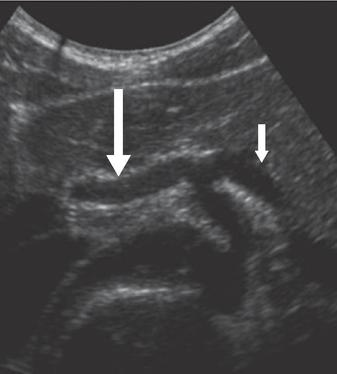

What is the long arrow  pointing at?

Hepatic artery

What is the short arrow pointing at?

Splenic Artery